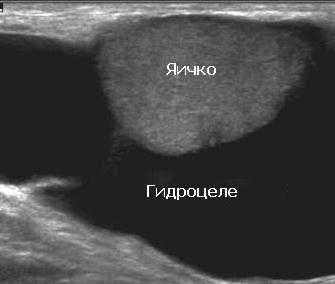

УЗИ яичек при водянке яичка дает возможность диагностировать гидроцеле в виде анэхогенного образования внутри мошонки.

На ультразвуковом изображении слева визуализируется нормальное яичко, окруженное влагалищной оболочкой. Справа яичко окружено гидроцеле - между париетальным и висцеральным листками находится большое количество жидкости.

Гидроцеле может быть настолько большого размера, что при пальпации врач не может определить нахождение яичек. В этом случае УЗИ помогает определить локализацию яичка.